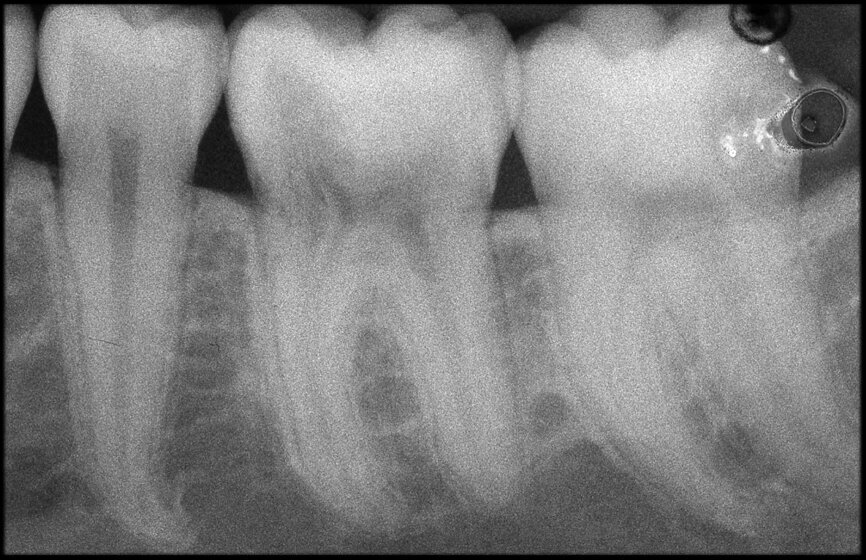

The situation was entirely different for the mandibular premolar shown in Figures 7 to 9, where, in the absence of any radiological signs of a lesion and despite the apparently correct endodontic approach adopted by another colleague, the patient complained of persistent pain which was both spontaneous and triggered by percussion of the tooth. In this case, the previous excellent root canal therapy would suggest an endodontic surgery approach, which could guarantee a higher success rate than retreatment. Given this diagnostic doubt, it was decided to perform a 3D study, which revealed an endodontic lesion caused by an untreated lingual canal. This correct diagnosis, thus, made it possible to perform selective intervention on the remaining pulp, leading to successful treatment of the untreated canal.